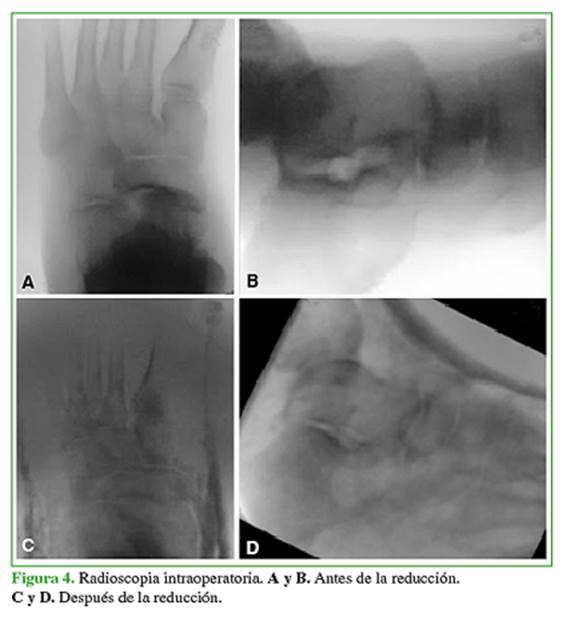

Se decidió realizar la reducción cerrada urgente en el quirófano bajo anestesia general. Para relajar el tendón de Aquiles se efectuó la maniobra de flexión de rodilla. Se aplicó tracción en el eje, acentuando la deformidad, en primer término, para desimpactar y luego llevando el pie a la eversión, se consiguió la reducción. Se constató la adecuada reducción bajo radioscopia (Figura 4), se le colocó una bota corta de yeso, y se tomaron radiografías de control posoperatorias (Figura 5).